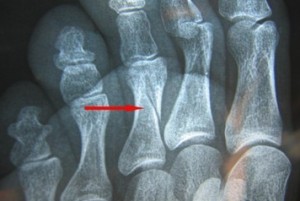

Подобные травмы встречаются очень часто. В большинстве случаев, они возникают из-за прямого воздействия травмирующей силы. Например, когда на конечность падает тяжелый предмет или стопу переезжает колесо. Выделяют два вида – одиночные и множественные. Кроме того, существуют еще и переломы шейки и головки плюсневых костей.

Если это одиночный перелом, то конечность отекает на тыле, при прощупывании выявляется незначительная боль. Если же это множественные переломы, то отек наблюдается всей стопы, а также присутствует сильная боль. Иногда случается деформация стопы. Диагноз может подтвердить доктор, перед этим пациент должен осуществить рентгенографию в двух проекциях.

Если это травма без смещения костей, то доктором накладывается гипсовая шина. Обычно срок реабилитации варьируется в пределах от трех до четырех недель. Впрочем, восстановление может занять меньший срок в том случае, если строго выполнять все рекомендации доктора. Если же смещение произошло, то выполняют закрытое вправление и скелетное вытяжение. В таком случае, срок фиксации составляет шесть недель. При подобной травме накладывается специальная шина, которую еще называют «с каблучком».